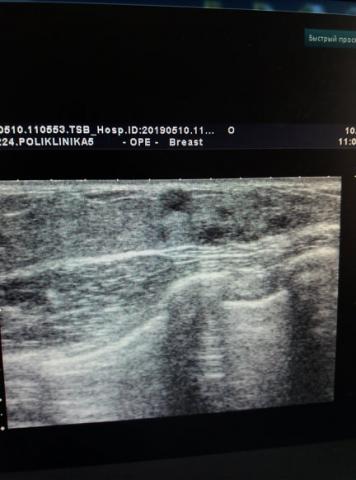

Ми ПЕРШІ в Черкаській області, хто запровадив та здійснює найсучасніший вид ультразвукового дослідження – фіброеластометрію зсувної хвилі та компресійну еластографію (мультипараметрична діагностика). Фіброеластометрія зсувної хвилі дозволяє швидко та якісно встановити ступінь фіброзу печінки за шкалою metavir (кількісний аналіз), а компресійна еластографія дає можливість з високою точністю діагностувати ступінь злоякісності новоутворень (якісний аналіз).

Фіброеластометрія зсувної хвилі та компресійна еластографія

Ми перші в Черкаській області, хто з середини 2018 року здійснює найсучасніший вид ультразвукового дослідження – фіброеластометрію зсувної хвилі та компресійну еластографію.